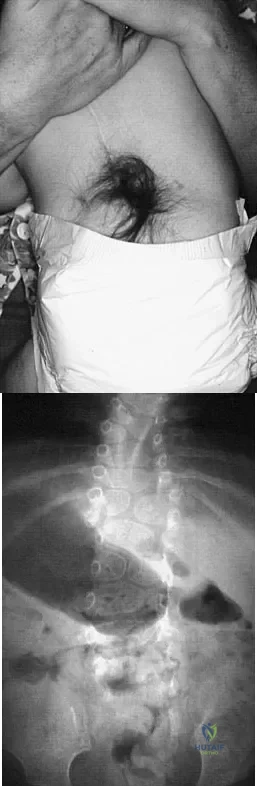

Question 71

A 4-month-old infant is referred for evaluation of congenital scoliosis. The child has no congenital heart anomalies, and a renal ultrasound shows that he has one kidney. Examination reveals mild scoliosis and a large hairy patch on the child's back. Neurologic evaluation is normal for his age. A clinical photograph and radiograph are shown in Figures 19a and 19b. Initial management should consist of

Explanation